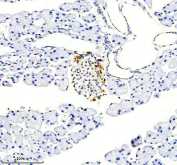

Somatostatin 28 Antibody. Immunohistochemistry analysis of formalin-fixed, paraffin-embedded mouse pancreas tissue using a rabbit Somatostatin 28 antibody. Heat-induced antigen retrieval was performed in EDTA buffer at pH 8.0. The section was blocked with goat serum and incubated with primary antibody overnight at 4oC, followed by a peroxidase-conjugated goat anti-rabbit IgG secondary antibody. Cytoplasmic HRP-DAB brown staining is observed in islet cells within pancreatic tissue, consistent with Somatostatin 28 expression in endocrine cell populations.